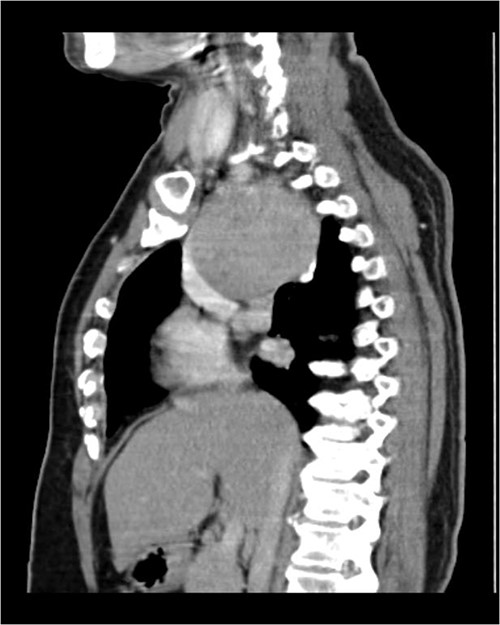

A 57-year-old female came with chest discomfort and cough since 1 month. The chest X-ray (Fig. 1) showed mass in the superior mediastinum. CECT thorax (Fig. 2) revealed the soft tissue density 7 cm × 7 cm (Fig. 3) in superior mediastinum abutting subclavian artery, azygous vein, anteriorly displacing superior venacava, anteromedially abutting arch of aorta, posteromedially compressing trachea and abutting right main bronchus. A 4.9 cm × 5 cm mass in the left side superior mediatinum was seen abutting internal jugular vein and brachiocephalic artery. USG showed the presence of normal thyroid in the neck. CT guided biopsy from the right mass showed ectopic thyroid tissue (ETT)-colloid goiter. Due to close proximity with major vessels sternotomy done. Mass in the left side 5 cm × 5 cm (Fig. 4) in the superior mediastinum was identified, on dissecting superiorly, which was free from the thyroid in the neck and abutting the IJV, brachiocephalic artery and left innominate vein that were separated with meticulous dissection.

CECT scan showing the right side mass displacing superior nn(SVC).